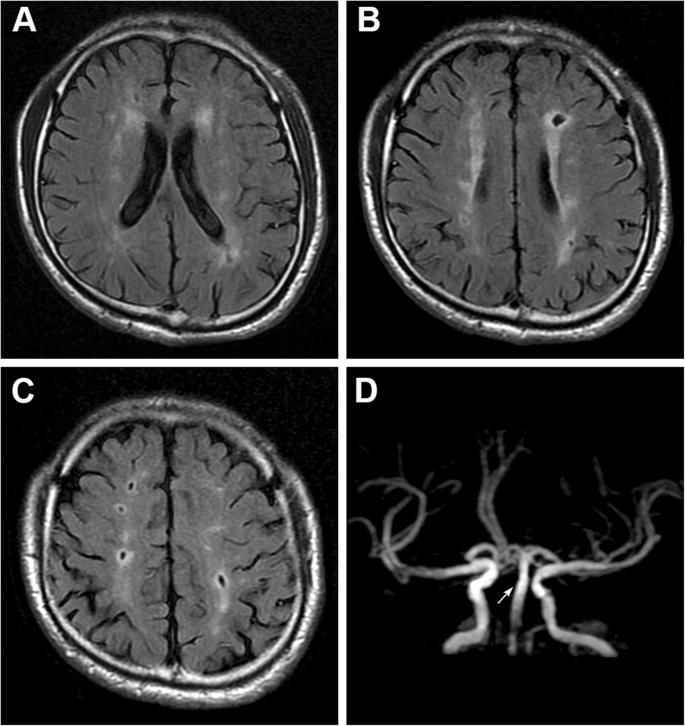

四、脑白质脱髓鞘。

面对一份头部的CT报告单,最常见的字眼其实就是脑白质脱髓鞘了,对于这种问题该怎么解决呢?

其实对于大多数患者来说,并不需要解决。

看上去脑白,质脱髓鞘是一种疾病,可是实际上只要岁数到了,或多或少都会有这种情况,轻度的脑白质脱髓鞘在55岁以上的人群当中其实是很常见的。

当然,很多人虽然有脑白质脱髓鞘,但并没有什么症状也没有什么感觉。

对于这类患者其实并不需要治疗,症状较轻的时候也没有什么好的治疗方式可以改善,最重要的就是强调改善生活方式,把自己大脑子的状态调整好。

但是要小心,如果是非常严重的脑白质脱髓鞘可能就是一种疾病了,我们也应该好好的治疗,比如脑神经炎,而且出现头痛。